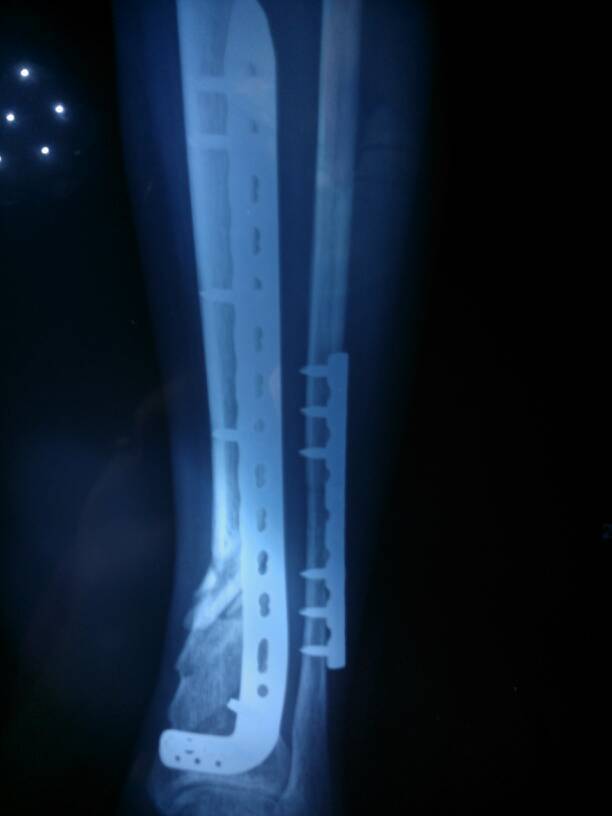

女,26岁,2013年11月23日因车祸左小腿两根骨头粉碎性骨折 12月六日出院,现以五个月 五月 女,26岁,2013年11月23日因车祸左小腿两根骨头粉碎性骨折。12月六日出院,现以五个月。五月一日拍的片想问专家腿现在长的怎么样了。 点击展开 匿名用户 2014-05-17 18:21 为您推荐: 其他回答 病情分析: 现在还是有点没有愈合的。 指导意见: 建议定期复查查看情况,平时要注意补充营养,合理的治疗。 匿名用户 2014-05-17 20:07 相关问题 去年8月份因车祸导致左边锁骨粉碎性骨折,医院给固定了… 小腿粉碎性骨折术后快五个月了,小骨头还痛,用手摸还麻痒,站起来脚也是这样是什么原因,三个月拍片时没 右肩锁骨粉碎性骨折算几级?车祸